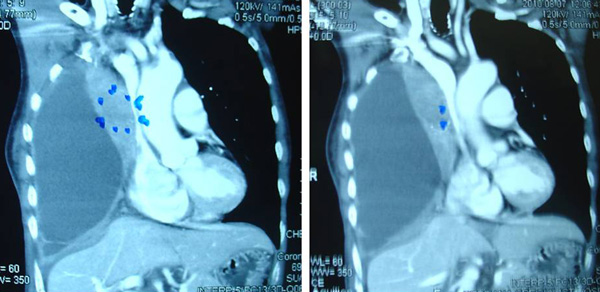

Guat (T672) is a 53-year-female. In 2006, she had been coughing out blood for the whole year. In September 2007, Guat underwent an operation to remove her appendix. Her throat was swollen after this operation. MRI of her neck on 7 October 2007 showed normal nasopharynx and thyroid. However, there was an irregular lesion at the right upper lobe of her lung.

A CT scan on 9 October 2007 showed 2 focal cavitating lesions at the right upper lobe and left lower lobe of her lung, suggestive of pulmonary tuberculosis (TB). There was also a small fluid density collection at right iliac fossa probably due to hematoma from previous appendix operation.

A biopsy of the right pulmonary nodule done indicated malignant melanoma. A second opinion was sought and Guat was subsequently diagnosed with malignant tumour metastatic to lung. Possibility of malignant melanoma is very strong.

The doctor told Guat that her condition was very serious. She had a Stage 4 cancer. The doctor also said, In my 15 years of experience, this is the only case that I have seen. According to the doctor this cancer originated from a mole but Guat searched her entire body and could not find any mole. Surgery is not indicated for this cancer. However, the doctor stressed that it is better to start treatment. Without radiotherapy it may spread to her brain. Currently, medicine is much more advanced and Guat might benefit from this treatment. Guat refused and came to seek our help on 2 November 2007.